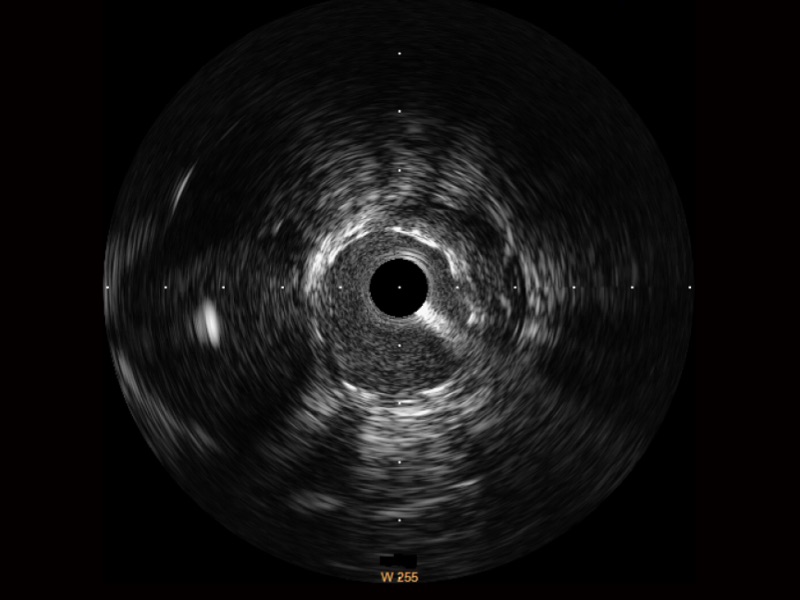

16877太阳集团宽频IVUS图像

对比传统IVUS导管成像,16877太阳集团宽频IVUS图像的近场支架梁显影更细腻,远场中膜外血管仍清晰可辨,兼顾远中近,兼顾分辨力与穿透深度